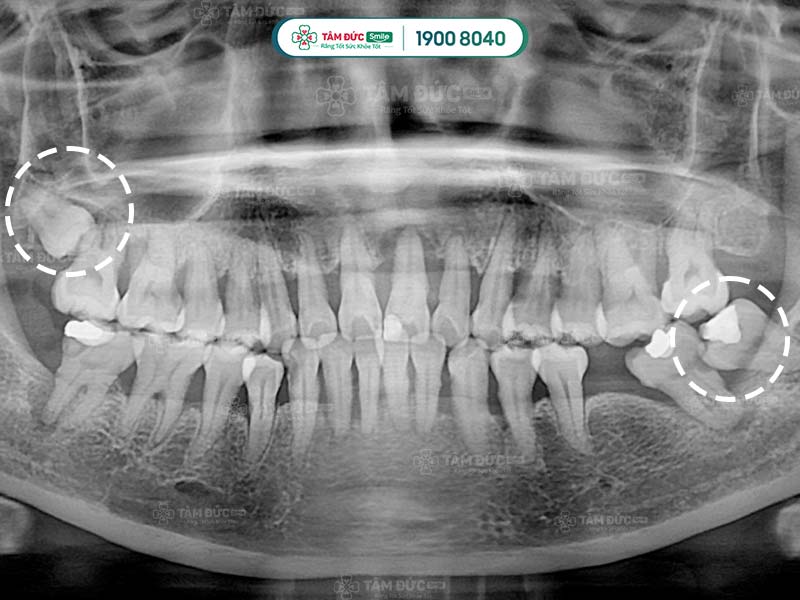

Trên cung hàm, răng khôn là chiếc răng mọc lên sau cùng, khi các chiếc răng khác đã ổn định vị trí. Cung hàm không có đủ không gian cho răng khôn phát triển, làm răng khôn mọc lệch, mọc ngầm, hoặc mọc đâm ngang vào răng số 7,... Tất cả các trường hợp đều làm cho Quý khách cảm thấy khó chịu, vì vậy cần nhổ răng khôn để giải quyết.

- Răng khôn mọc gây đau, gây u nang hoặc nhiễm trùng, nguy cơ làm ảnh hưởng các răng kế cận.

Răng khôn mọc lệch nên nhổ từ sớm